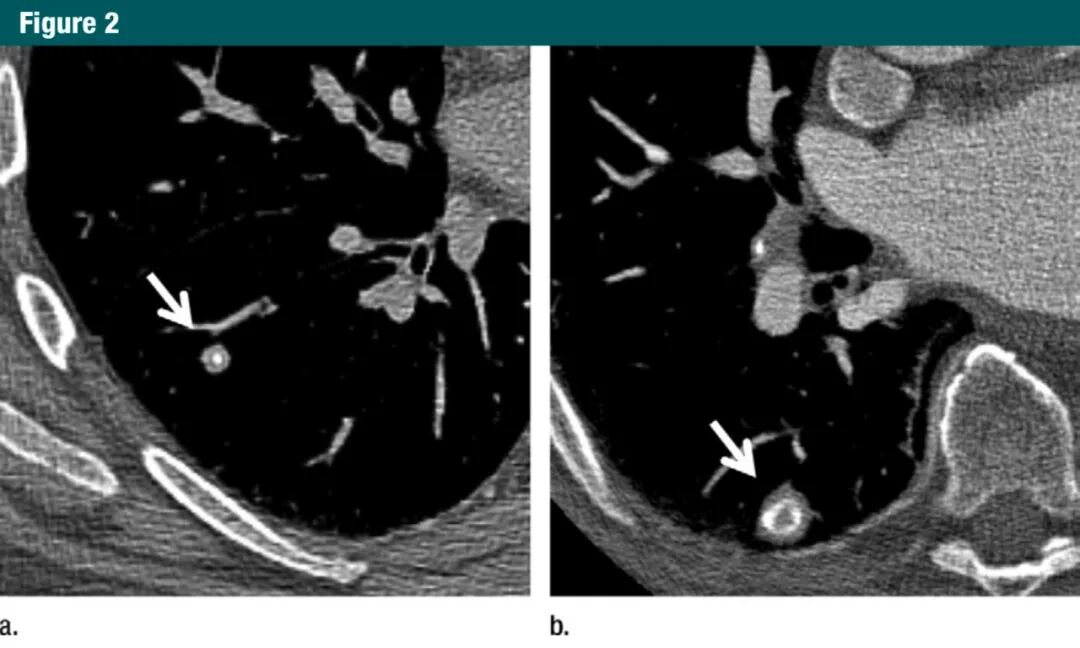

图2 :a.CT图像显示一个边缘光滑的实性结节、中央钙化,为典型的已经愈合的肉芽肿,不建议进一步CT随访;b.CT图像显示边缘光滑的实性结节、内有层状钙化,为典型的已经愈合的肉芽肿,对于这种病灶,不建议进一步CT随访7Gc帝国网站管理系统

图3:a.5mm层厚CT显示左下叶一纯磨玻璃结节(箭头);b.同一部位和层面的1mm层厚CT显示,这是一个可疑的部分实性结节,其内有空泡(箭头)7Gc帝国网站管理系统

图4:a.横断面1mm层厚CT显示靠近水平裂的一个结节样致密影(箭头);b.CT冠状位重建显示该致密影是良性的线状疤痕或淋巴组织(箭头)7Gc帝国网站管理系统